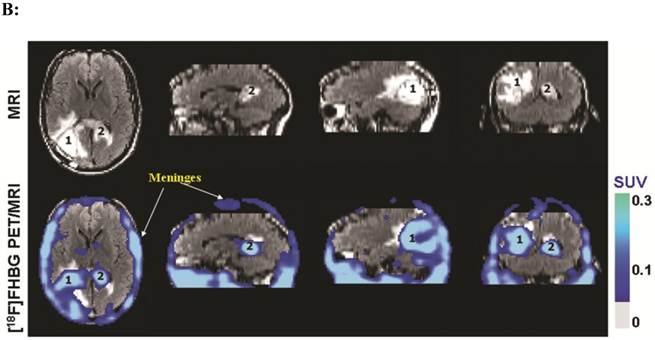

(A). Description of the procedures involved in the preparation of genetically engineered CTLs and their infusion into the recurrent glioma tumor resection site. (B). MRI and PET over MRI superimposed brain images of a patient recieving genetically engineered cytolytic T cells expressing HSV1-tk for imaging and safety purposes. Images were acquired approximately two hours after [18F]FHBG injection. The patient had a surgically resected tumor (1) in the right parietal lobe and a new non-resected tumor in the center (2), near corpus callosum of his brain. The infused cells had localized at the site of tumor 1 and also trafficked to tumor 2. [18F]FHBG activity is higher than the brain background at both sites. Background [18F]FHBG activity is low within the Central Nervous System due to its inability to cross the blood brain barrier. Background activity is relatively higher in all other tissues. Activity can also be observed in the meninges. The tumor 1/meninges and tumor 2/meninges [18F]FHBG activity ratio in this patient was 1.75 and 1.57, respectively. Whereas the average resected tumor site/meninges and intact tumor site to meninges [18F]FHBG activity ratio in control patients was 0.86 and 0.44, respectively. Figure 9A is a reprint of figure 13.9 from a book chapter by Penuelas et al.7 and Figure 9B is a reprint of figure 1 from a case study report by Yaghoubi et al.11

Theranostics Image Theranostics Image